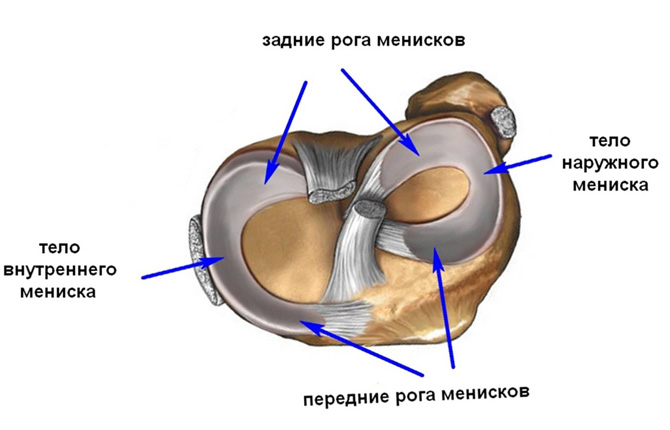

Анатомические изображения менисков и коленного сустава